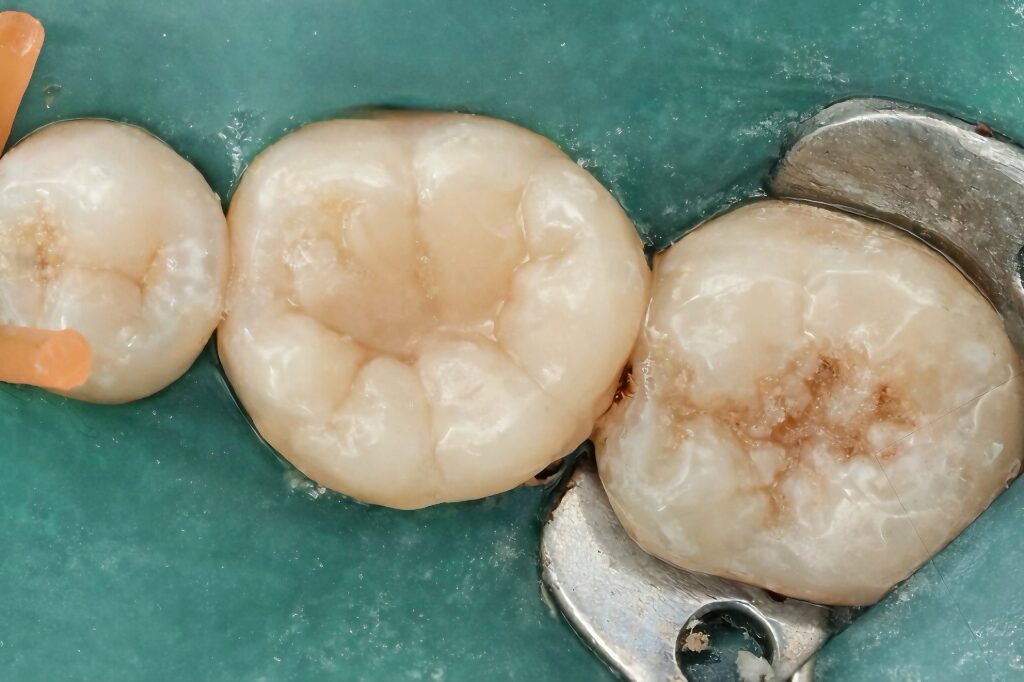

The onlay was built incrementally using a stress-reduced layering technique. Cusps were reconstructed anatomically, respecting occlusal morphology and functional pathways. Occlusion was carefully adjusted to avoid high-stress contacts, particularly in lateral excursions.

Finishing and polishing were performed to achieve smooth margins, proper contact areas, and a natural surface texture.

The final restoration provided immediate cuspal protection, an effective coronal seal, and restoration of occlusal function. Radiographic evaluation confirmed dense root canal obturation and proper adaptation of the restorative material.